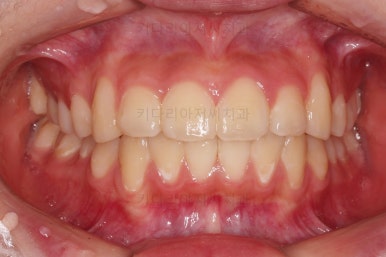

치료 마무리 사진입니다.

연산동치과 전후사진을 비교해 볼게요.

치열이 가지런해지고 교합도 좋아지고 웃는 모습도 매우 좋아졌네요.

비발치 덧니교정이었지만 입이 튀어나오거나 하지 않고 오히려 치아 각도나 입매가 약간 디ㅜ로 들어가면서 입매도 자연스러워졌어요.

충치치아도 깨끗한 치료가 되었고요.